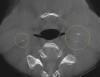

A comprehensive dental exam was performed that included a blood pressure test, an oral cancer screening, intraoral photographs, full mouth radiographs, a periodontal chart, a saliva test, and a CBCT scan. The exam confirmed the presence of active dental decay, periodontitis (ie, stage III, grade B), and areas of calcifications in his carotid artery (Figure 1 through Figure 3).

(2.) CBCT axial view of carotid calcifications.

Figure 2